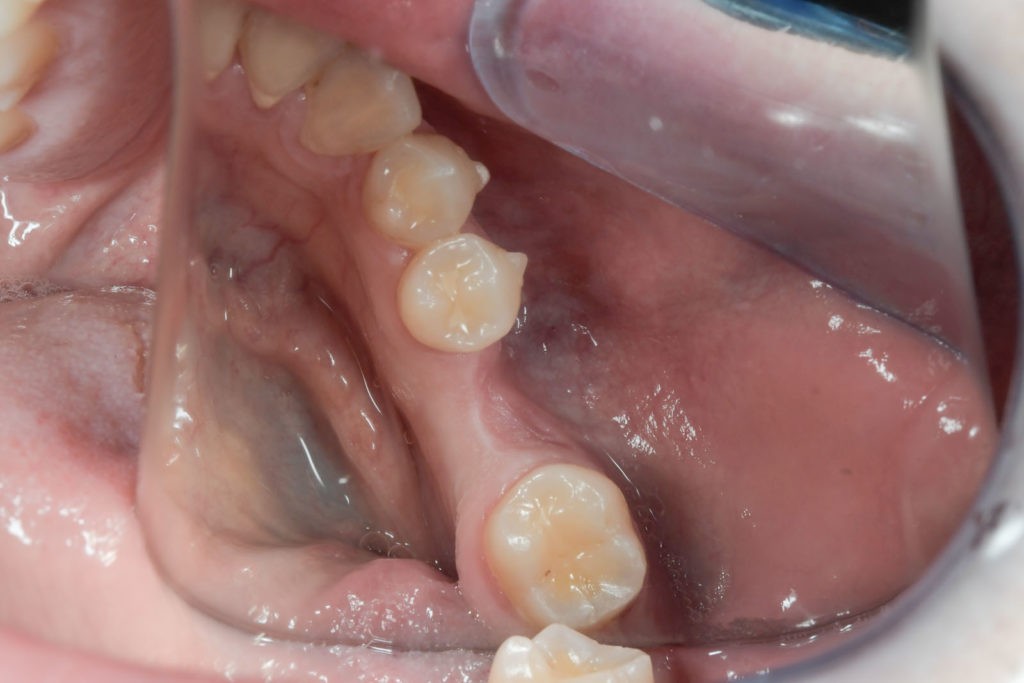

Przed podjęciem leczenia należy określić stopień zaniku kości szczęk oraz żuchwy. W tym celu przeprowadza się badanie kliniczne oraz odpowiednią diagnostykę obrazową pacjenta. Uwzględnia ona zdjęcie panoramiczne OPG jako podstawę dwuwymiarowego obrazowania podłoża kostnego oraz możliwe jest badanie tomograficzne CT lub bardziej precyzyjna tomografia stożkowa CBCT. Opcjonalnie wykorzystywana diagnostycznie tomografia pozwala na bardziej wnikliwą ocenę stopnia zaniku kości w trójwymiarowym, przestrzennym obrazie.